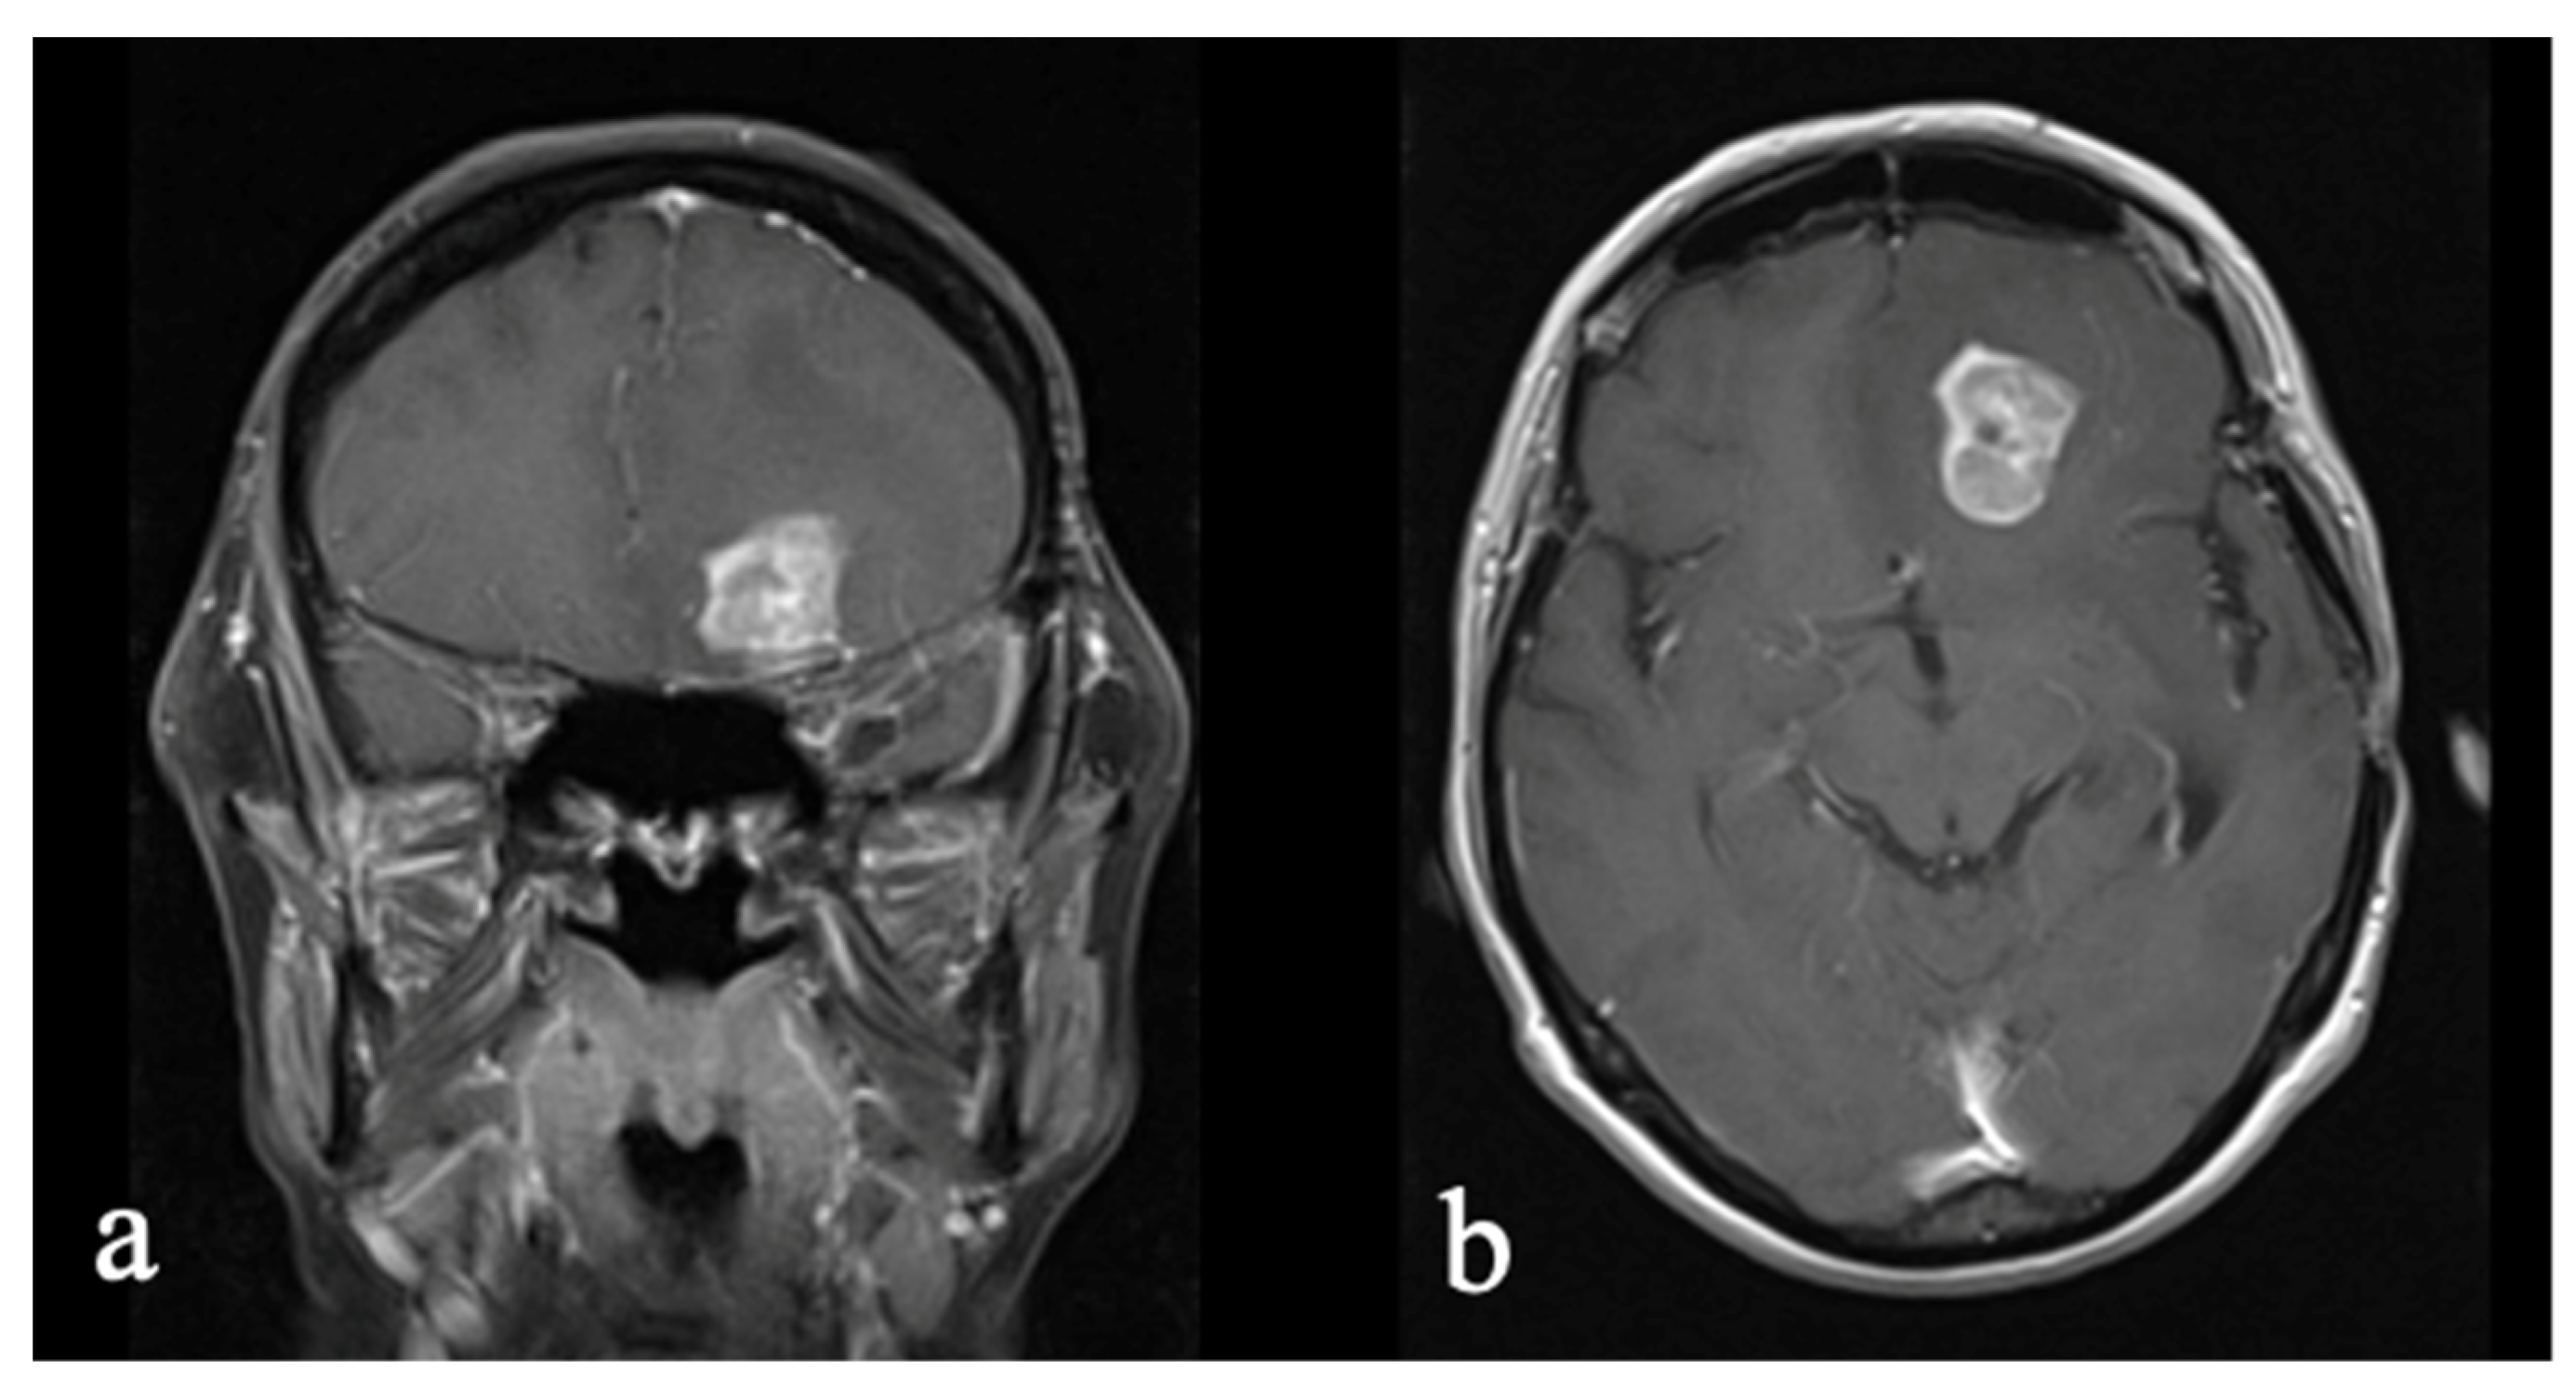

3.4. Case 4: Glioblastoma to Low-Grade, SEGA-like Astrocytoma

3.4.1. Initial Diagnosis

3.4.2. Molecular Profiling and Treatment Timeline

| 4 | Glioblastoma → SEGA-like astrocytoma | 24/F | NEC | NF1; t-SNE proximity to pilocytic astrocytoma | ~3 years | Chronic pain, fatigue | EQ-VAS: 75%; Distress: 3/10; EQ-5D-5L: pain: moderate problems | 80 |